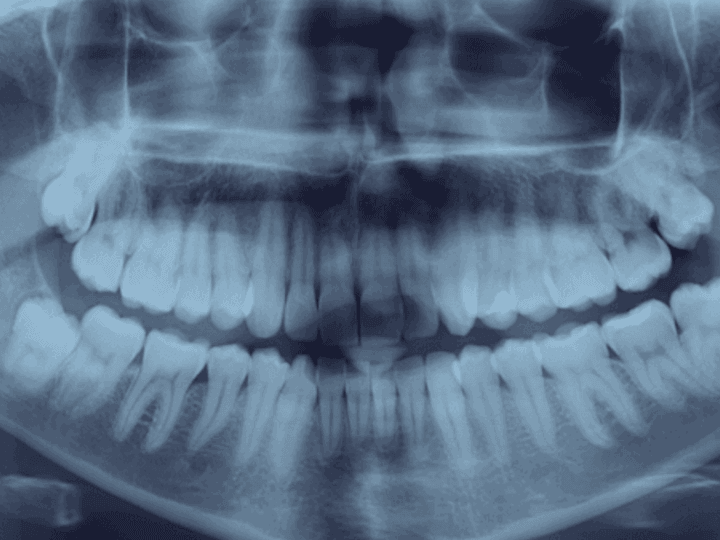

Найважливіше при екстракції – попередня комплексна діагностика. Перед процедурою лікар обов’язково направляє пацієнта на комп’ютерну томографію (КТ).